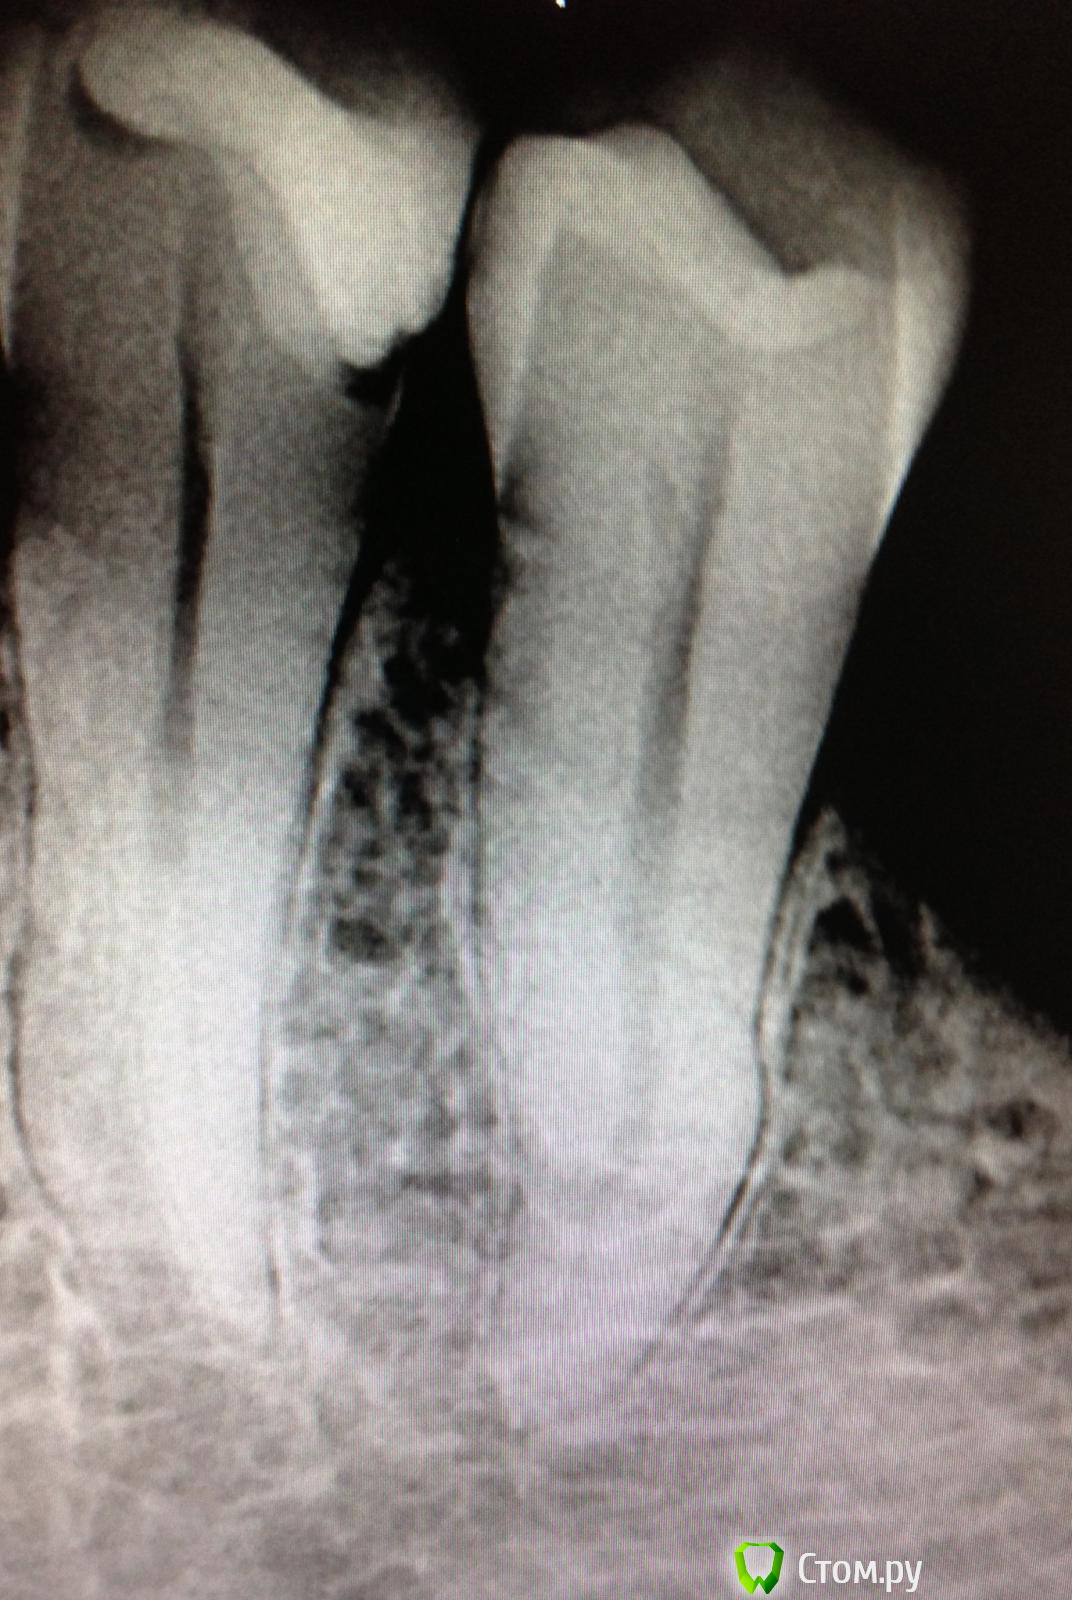

SSTi Опубликовано 26 мая, 2014 Автор Поделиться Опубликовано 26 мая, 2014 " Керамические "пульпиты( депульпировал по мк). 45. Дистально старая пломба. Доступ. Коффер. Протейперы машинные до ф2, профайлы, стоп упор 30.02. Гипохлор, аш два о, хлоргексидин. Уз. Латералка. 35. Стоп упор 40.02. Ссылка на комментарий